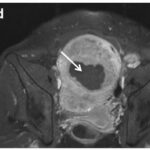

Best practice recommendations for glioma imaging

Based on a large survey conducted in Europe, the authors elaborate on recommendations for relevant MRI protocol in patients with glioma, including basic and advanced techniques. This paper is dedicated to the whole imaging community in order to adapt a standard...